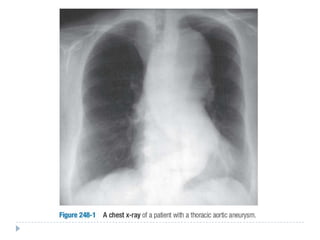

 Radiografía de tórax: aumento del

diámetro mediastinal,

desplazamiento o compresión de la

tráquea y bronquios prinipales